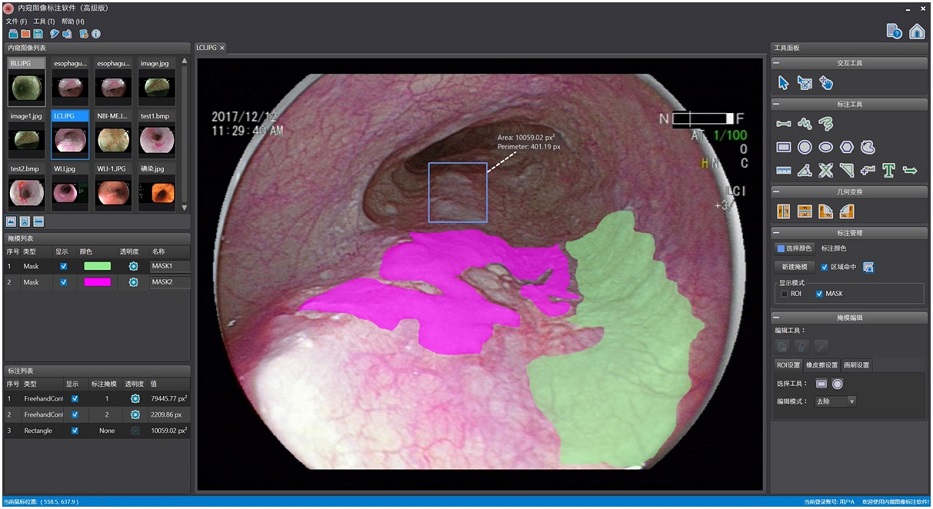

内窥图像标注软件(MISAT-Endo)

病理图像标注软件(MISAT-Patho)